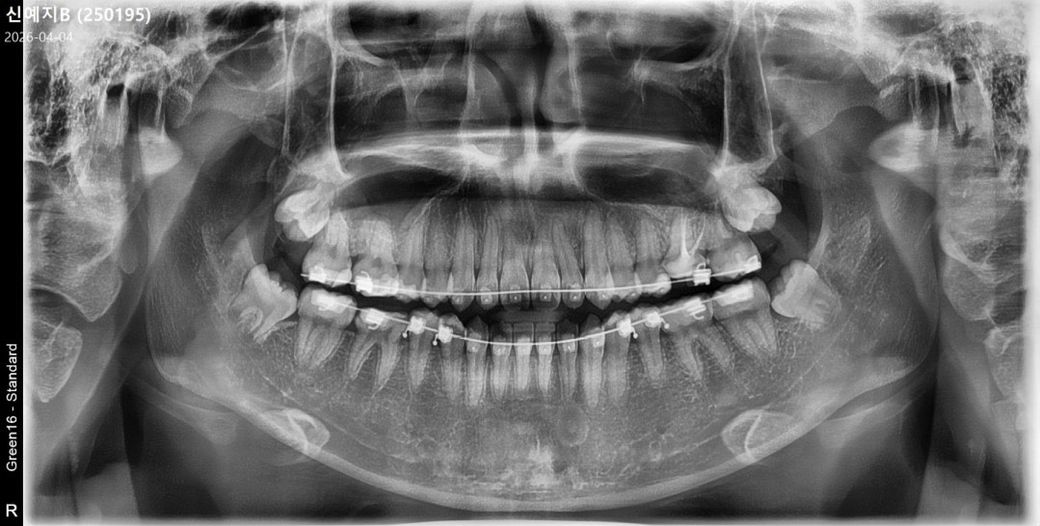

교정 1년 정도 진행 중인데

입이 약간 나와있고 약간의 주걱턱입니다.

발치교정을 하고 싶은데

앞니 뿌리가 짧아 최악의 경우 앞니가 빠질 수도

있다고 해서 고민입니다

아직 10대라서 비발치를 하는게 나을지

판단이 너무 어렵습니다

치열을 발췌하게 되면 악골을 좀 더 공간 확보가 쉬워지기 때문에 치아를 안쪽으로 넣는 것이 더 수월해지게 됩니다.

발치를 않했을 경우에는 치료를 마쳤을 경우 입이 원하는 대로 들어가지 않을 가능성이 있습니다.

비발치로 가능한 정도로 가용공간이 나온다면 당연히 비발치로 하는 것을 추천합니다 주걱턱은 발치교정한다고 완전히 해결되진 않습니다